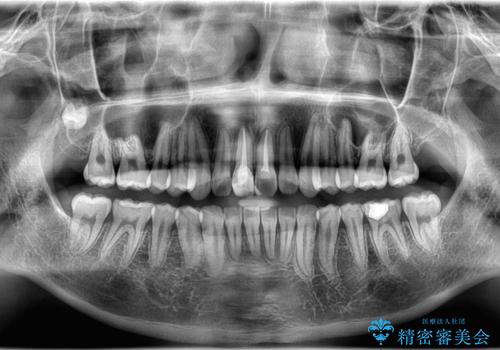

- 「歯のでこぼこを治したい 1年くらいで矯正を終わらせたい」を主訴に来院された患者様です。

叢生量は多く無く歯の傾斜も標準傾斜だったので歯は抜かずにワイヤー矯正で治療を行いました。

左側は2級傾向が強く臼歯の遠心移動をご提案しましたが、1年以内に矯正を終わらせたいという患者様のご意向で希望されず叢生を改善する矯正となりました。